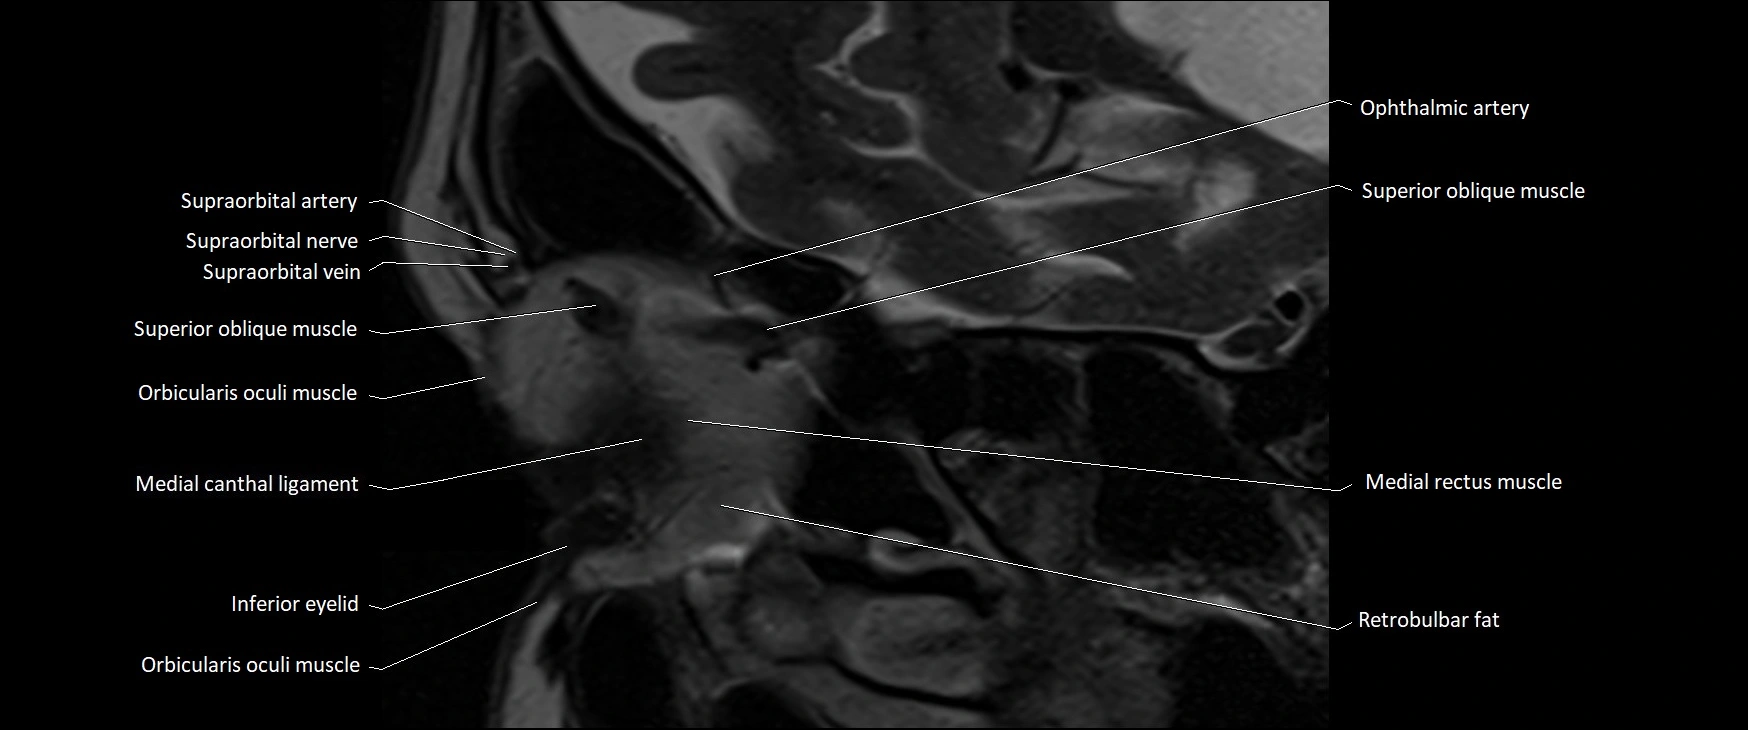

- Supraorbital artery

- Supraorbital nerve

- Supraorbital vein

- Superior oblique muscle

- Orbicularis oculi muscle

- Medial canthal ligament

- Inferior eyelid

- Medial rectus muscle

- Retrobulbar fat